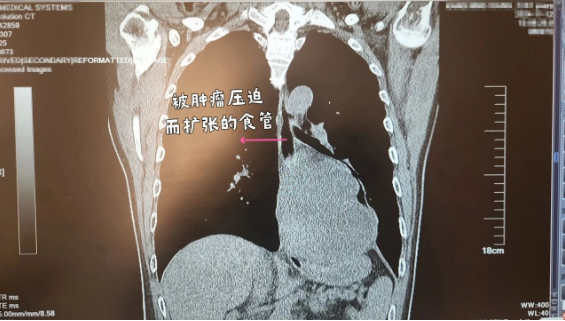

随着时间的推移,下肺静脉上的肿瘤被一点点剥离,随后,这根最关键的血管也被手术团队阻断。这时候,新的问题又出现了。老康的食管被肿瘤侵犯的程度远远高于影像学检查能够显示出来的程度,如果选择保留食管,那么肿瘤无法切除干净,存在很大的复发风险。

“我们原本打算尽可能为患者保留食管,但是在这种情况下,我们当机立断采取备用方案,把被侵犯的食管一起切除,同时进行食管胃吻合手术。”陈雯辉介绍,这相当于在完成肿瘤切除手术后,又进行第二台手术。